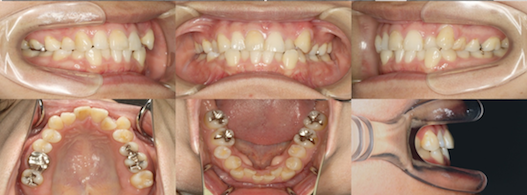

為您介紹隱適美矯正的治療案例。

※案例圖片著作權:隱適美醫師網(禁止轉載)

從案例照片的矯正前後對比中,可以清楚地看出其效果。